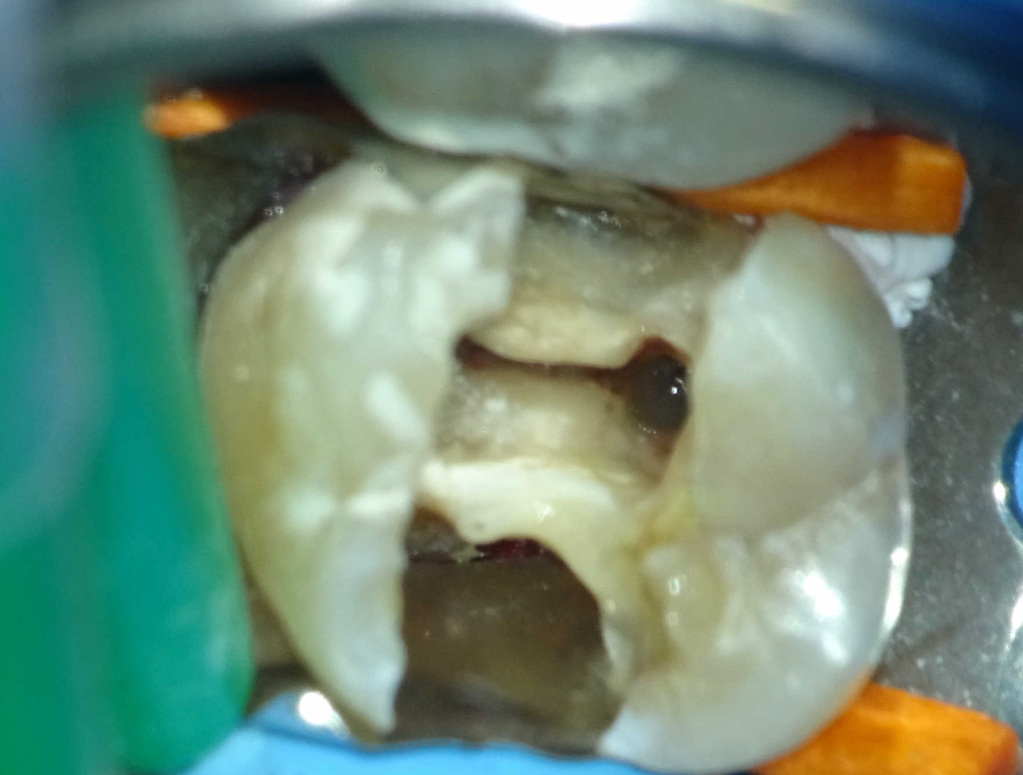

Diagnóstico de fisuras y fracturas

Diente fisurado, no tratable